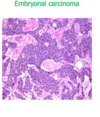

choriocarcinoma

Choriocarcinoma differentiates towards extraembryonic tissue (placental). It secretes beta hCG. Responsive to chemotherapy

totipotent - diff toward placental

choriocarcinoma and mole

preceded by mole in 50%

rapidly invasive, widely metastatic

sheets of malignant cells recapitualiting primitive cyto-syncitiotrophoblast

no villi formation

high hCG

extremely responsive to chemo